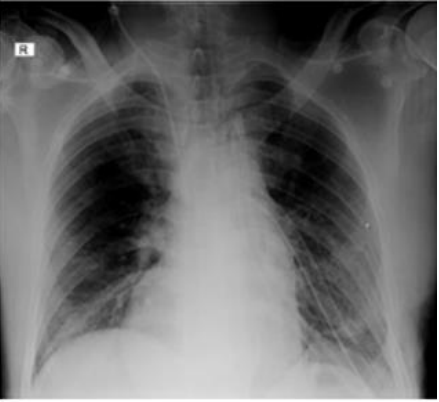

Following the intervention, the patient was transferred to the intensive care unit where he required management with invasive mechanical ventilation for 24 hours with subsequent extubation without complications. A control chest X-ray was taken with evidence of lung expansion and a centered trachea with no evidence of pneumothorax or hemothorax.

Image 6: Postoperative control chest X-ray